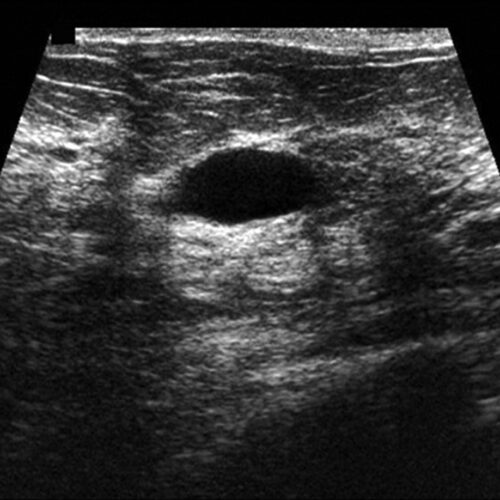

تشخیص کیست پستان

در بعضی مواقع ممکن است توده علائم شدید تری داشته باشد که باعث نگرانی در مورد سرطان سینه شود. در این زمان انجام یک سونوگرافی برای اطمینان از اینکه آیا توده جامد است یا فقط از مایع پر شده، الزامی است. اگر در گزارش سونوگرافی محتوای کیست جامد و یا جامد و مایع ( پیچیده ) باشد. برای اطمینان بیشتر از اینکه کیست سرطانی نباشد، انجام بیوپسی پستان مورد نیاز است.